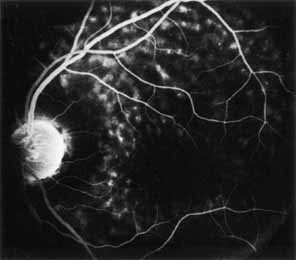

During the early stage of the dystrophy, when patients demonstrate a slight-to-moderate decrease in visual acuity and minimal color defects, there are minor or no visible fundus abnormalities. At most, the foveal reflex may be absent and there may be some increased granularity of the retinal pigment epithelium in the macula. Later, there is a decrease of visual acuity to the 20/400 range, oval atrophy of the macular retinal pigment epithelium (“beaten bronze” atrophy), and associated choroidal atrophy (Fig. 3). A characteristic bull's-eye maculopathy, similar to that seen in patients with chloroquine retinopathy, may also be seen.90 Photophobia, occasional nyctalopia, incomplete-to-complete color defects, and a central scotoma are often present. The symmetry of the process in both eyes is remarkable.